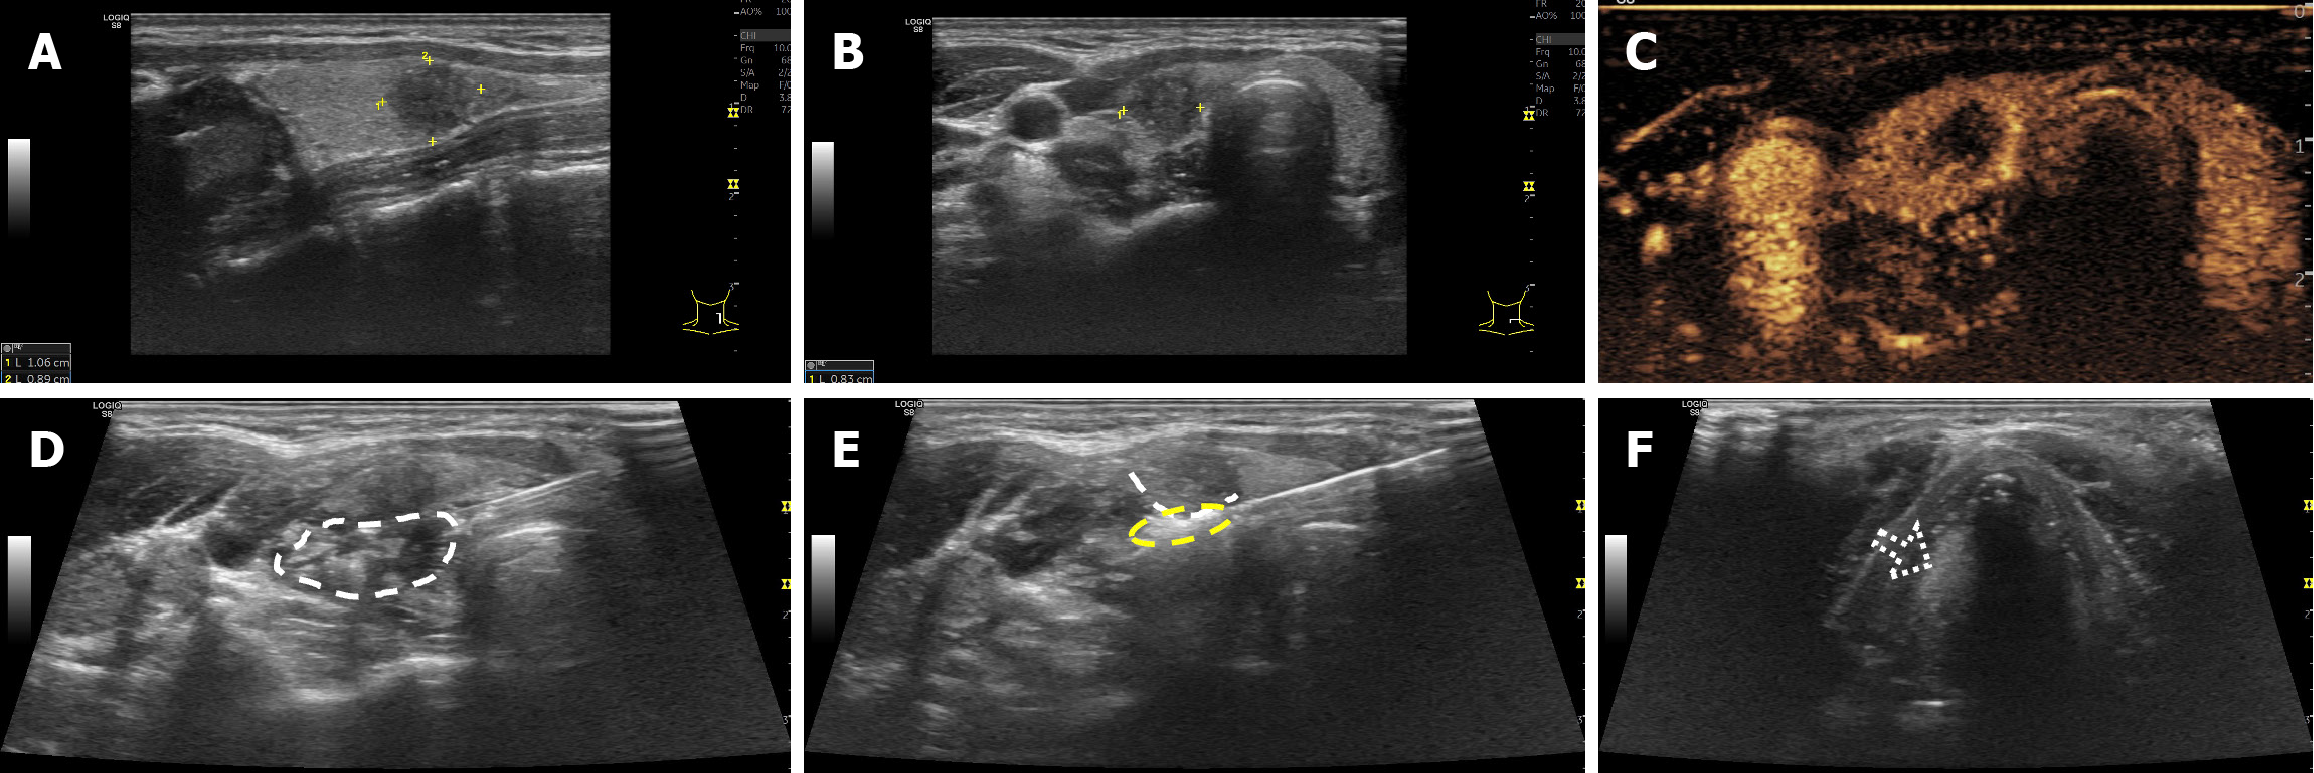

Figure 3 Microwave ablation without thermal field management in a 27-year-old woman with papillary thyroid carcinoma in the left thyroid lobe.

A and B: Longitudinal and transverse pre-microwave ablation ultrasound (US) images show a hypoechoic solid nodule measuring 11 cm × 0.9 cm × 0.8 cm; C: Pre-ablation contrast-enhanced US demonstrates hypoenhancement in the arterial phase; D: No effective fluid isolation zone was formed between the thyroid capsule and surrounding tissue (dashed circle); E: The active needle tip penetrated the thyroid capsule, and heat leakage (yellow dashed circle) was observed outside the capsule (dashed line); F: Immediately after treatment, the patient developed hoarseness; US revealed paralysis of the left vocal cord, fixed at the median position (dashed arrow).